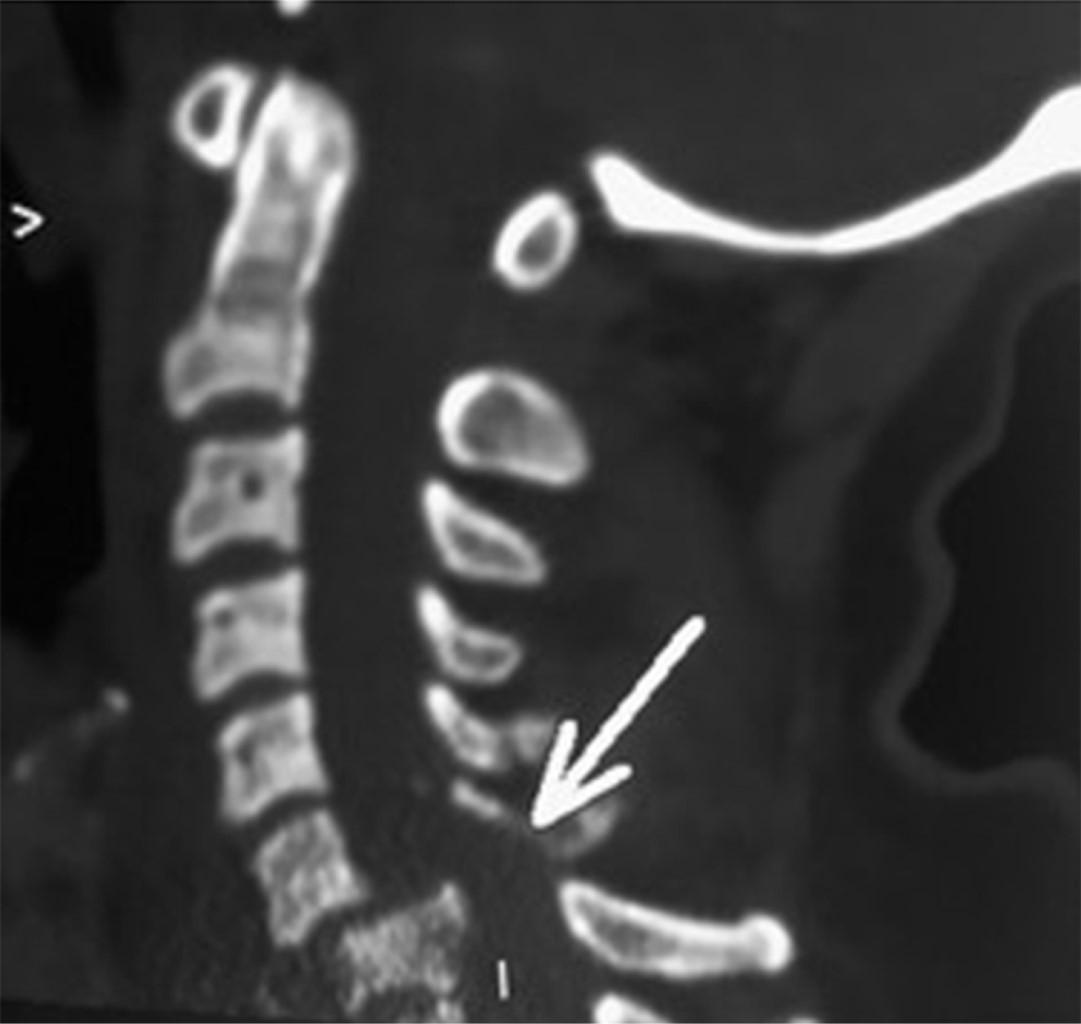

Paciente femenino de 46 años, se presenta en la sala de urgencias con politrauma secundario a accidente automovilístico. A su ingreso refería disnea, dolor de extremidades superiores e inferiores izquierdas y dolor cervical. A la exploración física se encontraba con inmovilización cervical con collarín rígido, saturación de oxígeno de 94% con mascarilla reservorio 10 L/min, presión arterial 74/52 mmHg, frecuencia cardíaca de 52 latidos por minuto, 18 respiraciones por minuto, Glasgow 15/15 con un peso de 88 kilogramos y estatura 1.54 metros (índice de masa corporal de 37.13). En el abordaje radiológico, la tomografía axial computarizada reveló una fractura multifragmentada de cuerpo vertebral de C7 con desplazamiento posterior cercano a 50% con disminución de la amplitud del conducto raquídeo (Figuras 1 y 2). Otros diagnósticos integrados fueron contusiones en hemitórax izquierdo, fracturas de tibia y peroné izquierdas y luxación de codo izquierdo.

Figura 2